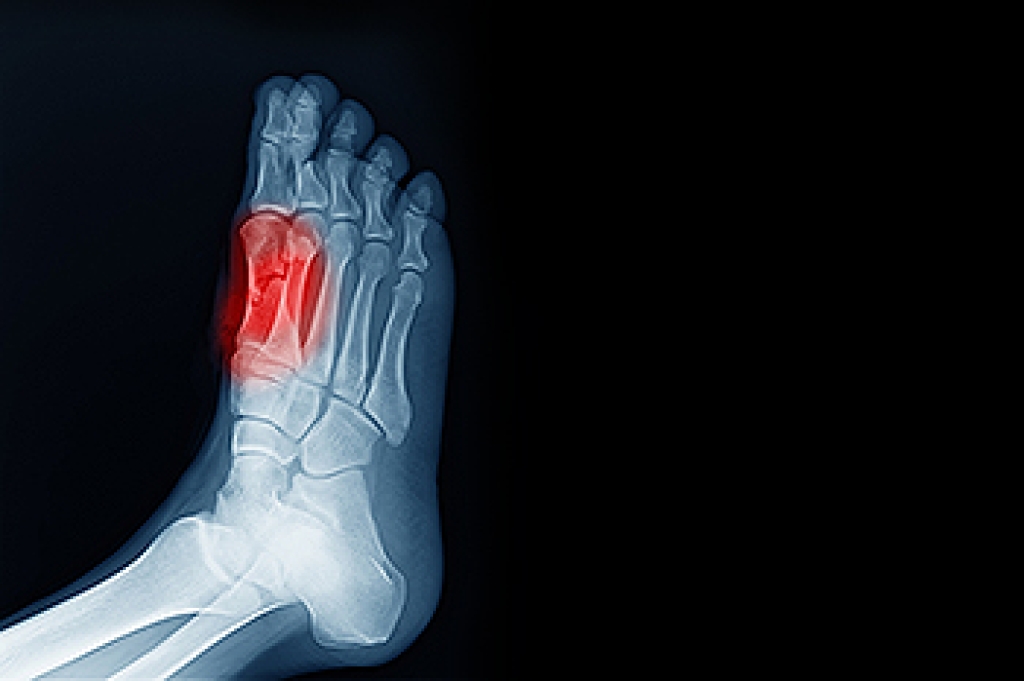

Sesamoiditis is a painful condition that affects the tendons around two small bones in the foot. These specialized bones, known as sesamoids, are unique in that they connect to muscles via tendons rather than to other bones. Typically, tendons become inflamed often due to overuse or repeated trauma, causing inflammation. This causes pain beneath the ball of the foot that gradually intensifies and may cause swelling or bruising. Certain activities, like running, basketball, or ballet, which impose considerable pressure on the ball of the foot, heighten the risk of developing sesamoiditis. Diagnosis involves a thorough physical examination to assess tenderness and limitations in mobility. A podiatrist will order imaging studies, such as X-rays, MRI scans, or ultrasounds to confirm the diagnosis and evaluate the extent of the condition. Treatment primarily focuses on lifestyle modifications, including modifying activity and changes in footwear. Pain management strategies such as custom orthotics and certain medications may also be prescribed. In severe cases where conservative measures fail, surgery may be necessary. If you are experiencing symptoms of sesamoiditis, it is suggested that you schedule an appointment with a podiatrist.

Sesamoiditis is a condition of the foot that affects the ball of the foot. It is more common in younger people than it is in older people. It can also occur with people who have begun a new exercise program, since their bodies are adjusting to the new physical regimen. Pain may also be caused by the inflammation of tendons surrounding the bones. It is important to seek treatment in its early stages because if you ignore the pain, this condition can lead to more serious problems such as severe irritation and bone fractures.